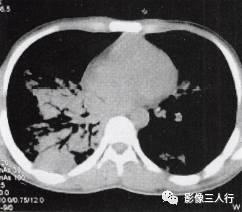

胸部CT图像显示,在含气少的致密肺的背景上见到含气的支气管,表现为两种形态: ①在大片肺实变病灶内的细条状空气密度影;②直径Imm的小泡状空气密度影,连续的几 个层面都能出现(图2、图3)。该征象表明:①近侧气道通畅;②肺泡内的空气经吸收(肺不张)或取代(肺炎、肺癌),或两者综合而消失。通畅含气的支气管在肺泡实变高 密度区内表现为管腔内低密度充气轮廓。